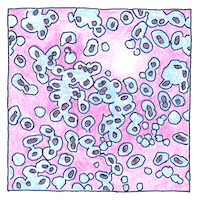

Pneumonia, lobar pneumonia is commonly caused by a bacterium, streptococcus pneumoniae, as discovered at the same time by George Miller Sternberg and Louis Pasteur ten years before the discovery of X-rays and fifty-five years before antibiotics.

Streptococcus pneumoniae, like other bacteria, is a resilient germ. Some strains have become resistant to some antibiotics. Pneumococcal conjugate vaccines for children have begun to reduce the risk.